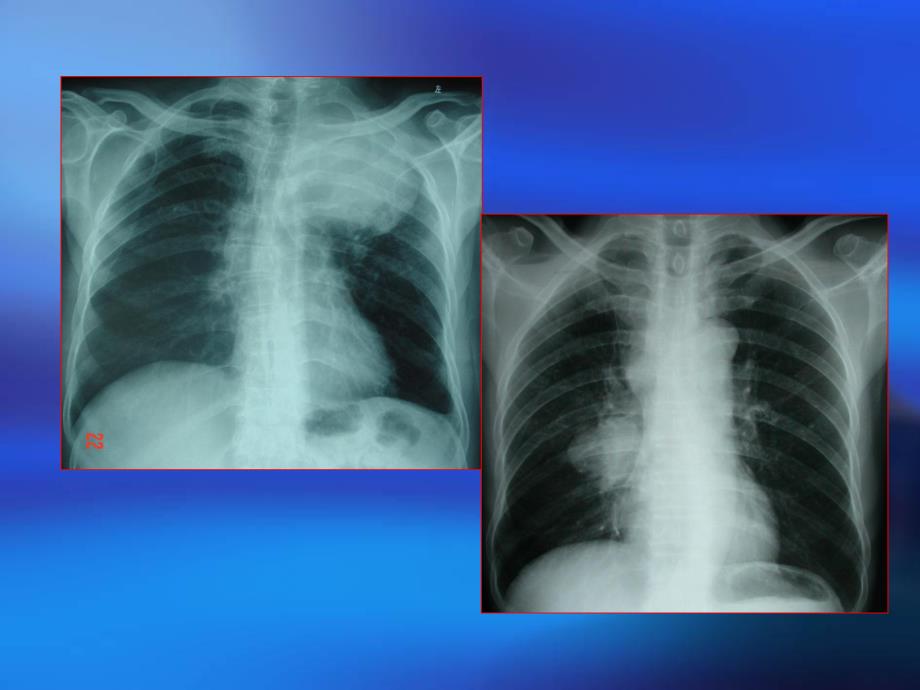

7、病方式 正常体格检查正常体格检查高危人群随访高危人群随访 刺激性咳嗽或咳嗽性质改变刺激性咳嗽或咳嗽性质改变 持续痰中带血持续痰中带血 反复同一部位肺炎反复同一部位肺炎 胸腔积液胸腔积液 单侧肩关节、上臂疼痛单侧肩关节、上臂疼痛 脑转移瘤脑转移瘤四、实验室检查四、实验室检查 (一)痰脱落(一)痰脱落细胞学细胞学检查检查 阳性率阳性率4080%(二)影像学检查(二)影像学检查1、X线检查线检查 段、叶性肺炎或不张段、叶性肺炎或不张 局限性肺气肿局限性肺气肿 肺门增大增浓肺门增大增浓 (1)中央型肺癌)中央型肺癌四、实验室检查四、实验室检查 圆形病灶(钱币状)圆形病灶(钱币状)分叶、毛分叶、毛 刺、

8、胸膜凹陷刺、胸膜凹陷 团块状阴影团块状阴影 偏心空洞、小泡征偏心空洞、小泡征 浸润样阴影浸润样阴影(2)周围型肺癌)周围型肺癌2、胸部、胸部CT 空间分辨率高,肿瘤内部结构及边空间分辨率高,肿瘤内部结构及边 缘征象显示好缘征象显示好 发现胸内隐蔽性病灶发现胸内隐蔽性病灶 纵隔与肺门淋巴结形态观察纵隔与肺门淋巴结形态观察3、MRI 碘过敏不能作碘过敏不能作CT者者 Pancoast瘤胸壁及臂丛神经受累瘤胸壁及臂丛神经受累 心包及大血管结构、上腔静脉综合征心包及大血管结构、上腔静脉综合征 鉴别肿瘤复发残留或是纤维化鉴别肿瘤复发残留或是纤维化4、PET 不显示组织解剖结构不显示组织解剖结构 探查局部